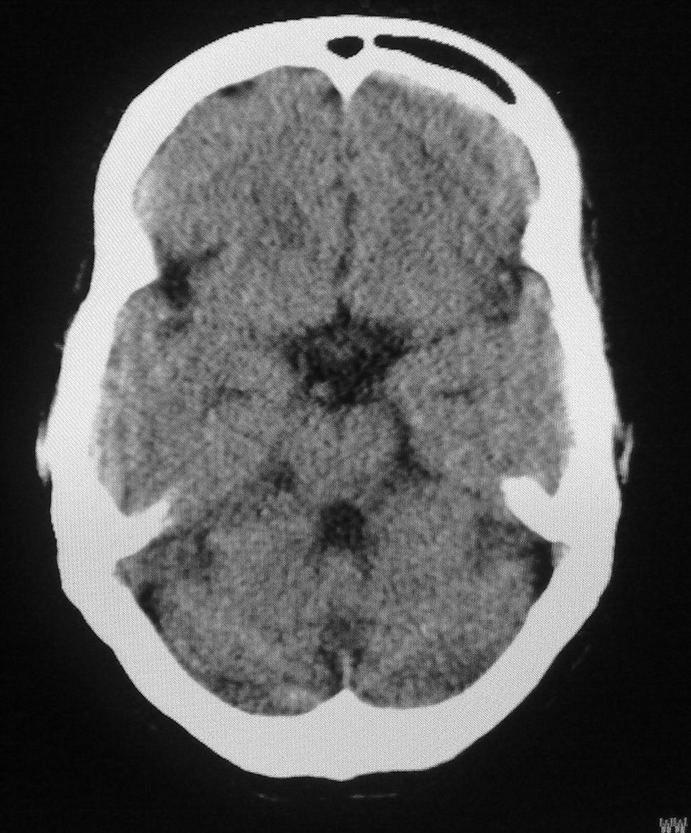

女,46岁,走路有时向一侧偏斜。是小脑萎缩吗?

小脑脑沟增多加深      为小脑萎缩引起的共济失调

小脑脑沟多于四条即为增多,又见加深,所以支持小脑萎缩。

从图像上看的确有轻度小脑萎缩征象,但患者才46岁,有外伤史吗?

小脑萎缩可能性大,建议mri检查。

小脑轻度萎缩